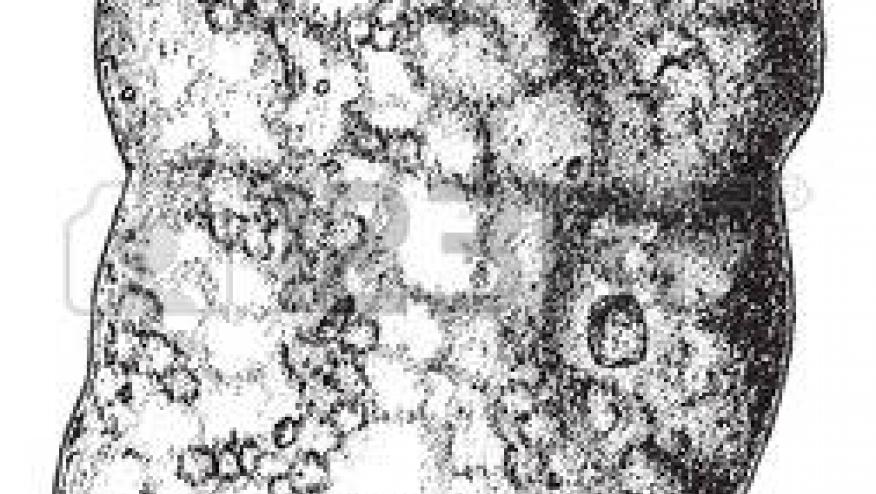

Renal biopsy demonstrated tubulointerstitial nephritis (TIN) in 93 patients (97.9%), with plasma cell infiltrates in the majority (75%). SSA (76.8%) and -SSB (53.8%) antibodies was frequently seen with TIN and was associated with a worse renal prognosis.

Glomerular lesions were found in 22 patients (23.2%), mainly related to cryoglobulin.